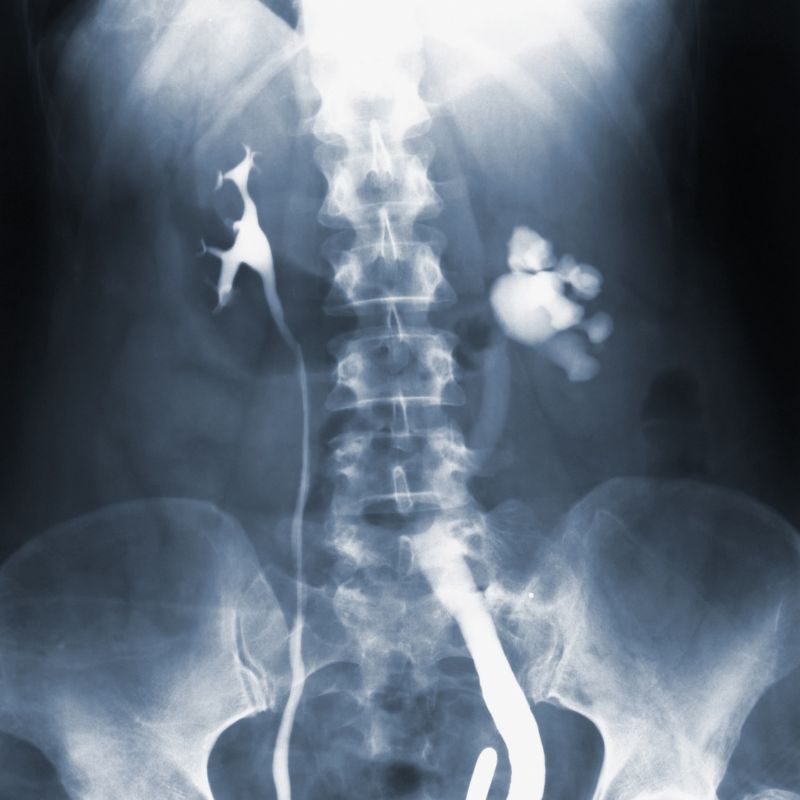

Los rayos X son un tipo de radiación electromagnética similar a la luz visible. Sin embargo, a diferencia de la luz, estos rayos tienen mayor